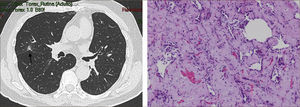

La masificación de los métodos de diagnóstico por imágenes, especialmente del TAC de Tórax, ha significado un importante aumento en la detección de NP pequeños, menores de 2cm, no visibles en la radiografía de tórax. Estos nódulos pueden ser tanto sólidos como sub-sólidos, cada uno tiene diferente comportamiento, velocidad de crecimiento y probabilidad de malignidad2,3 (Figuras 2 y 3).

El diagnóstico por imágenes mediante TAC de Tórax, cumple por tanto un rol fundamental en la identificación y caracterización de los nódulos pulmonares. Los cánceres pulmonares iniciales pueden presentarse como nódulos de diferente densidad: sólidos, cavitados, en vidrio esmerilado (VE: definidas como una intensidad discretamente mayor a la del parénquima pulmonar a través de la cual la vasculatura pulmonar es visible) o lesiones mixtas con componente sólido y VE. Figuras 2 y 33. En etapas más avanzadas los CPNCP se presentan como nódulos de mayor tamaño o masas (>3cms), sin embargo también pueden presentarse como lesiones consolidadas mal definidas, especialmente algunos adenocarcinomas productores de mucina. Estas lesiones pueden ser indistinguibles de una neumonía, pero a diferencia de estas persisten en el tiempo pese al tratamiento antibiótico 27,28.

Las lesiones Subsólidas tienen un mayor riesgo de malignidad que puede alcanzar un 18%51. Las lesiones subsólidas pueden corresponder a lesiones en Vidrio Esmerilado Puro (VE o GGO: Ground Glass Opacity) o a lesiones mixtas con un componente en VE y una zona sólida (Figuras 4, 5 y 6).

Asamura recientemente correlacionó también los hallazgos radiológicos con los histológicos en diferentes nódulos pulmonares pequeños. Las lesiones en VE puro corresponderían generalmente a Hiperplasia Adenomatosa Atípica (HAA), las lesiones mixtas (con componente en VE y sólido) a adenocarcinoma in situ y las lesiones mixtas en que el componente sólido sea mayor al 50% de la lesión corresponderían a adenocarcinomas invasores53.

Los nódulos en VE menores a 5mm generalmente corresponden a Hiperplasia Adenomatosa Atípica (HAA). Los nódulos en VE mayores pueden corresponder a HAA o Adenocarcinomas. Los CPNCP que se presentan como lesiones en VE puro (pure GGO) corresponden generalmente a adenocarcinomas in situ, adenocarcinomas tipo A en la clasificación de Noguchi54Figura 4.

Las lesiones mixtas (con componente en VE y sólido), son las que tienen la mayor probabilidad de malignidad, la que alcanza hasta un 63%51. Mientras mayor sea la proporción del componente sólido, mayor es la probabilidad de malignidad y peor el pronóstico. Estas lesiones corresponden a Adenocarcinomas micro invasores o invasores (Noguchi By C), Figura 4. Finalmente el desarrollo de un componente sólido en una lesión en VE o el aumento de la proporción del componente sólido en una lesión mixta en seguimiento indica su transformación en una lesión más agresiva50,51,53–57.